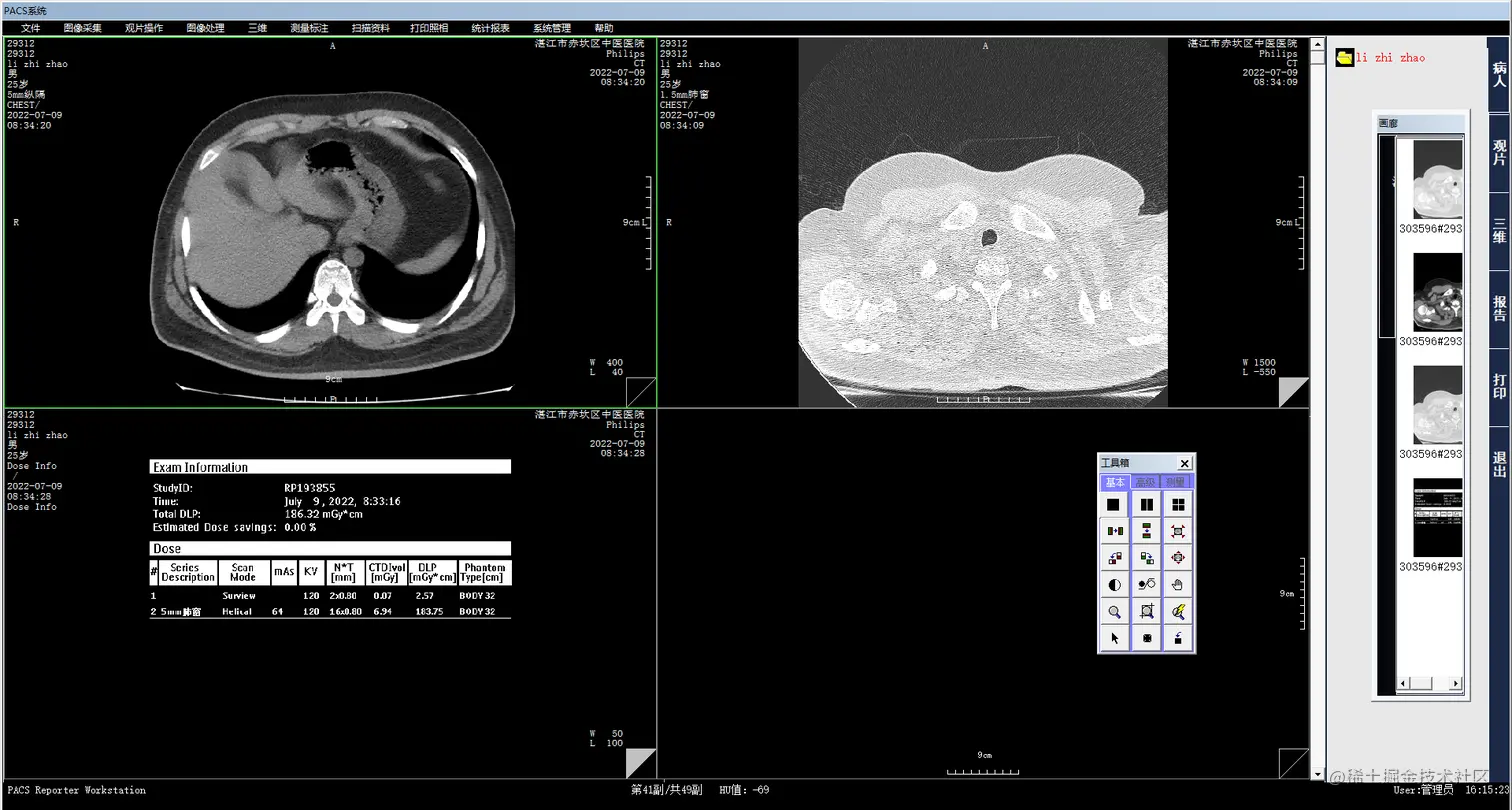

2.病人信息登记:用户可以在系统中登记患者的基本信息、影像信息和诊断结果等,系统将自动将这些信息与医生的处方信息进行匹配,避免信息混乱和重复。

3.计算机阅片:影像医生可以通过系统的计算机阅片功能,快速、方便地浏览患者的影像资料,并进行快速的诊断和处理。系统将自动生成电子报告,并将报告发送给相应的医生和护士。

4.电子报告书写:影像医生可以通过系统的电子报告书写功能,在线撰写电子报告,并将报告发送给相应的医生和护士。报告的内容将根据不同类型的检查和诊断结果进行自动生成,并且可以进行批量导出和打印。